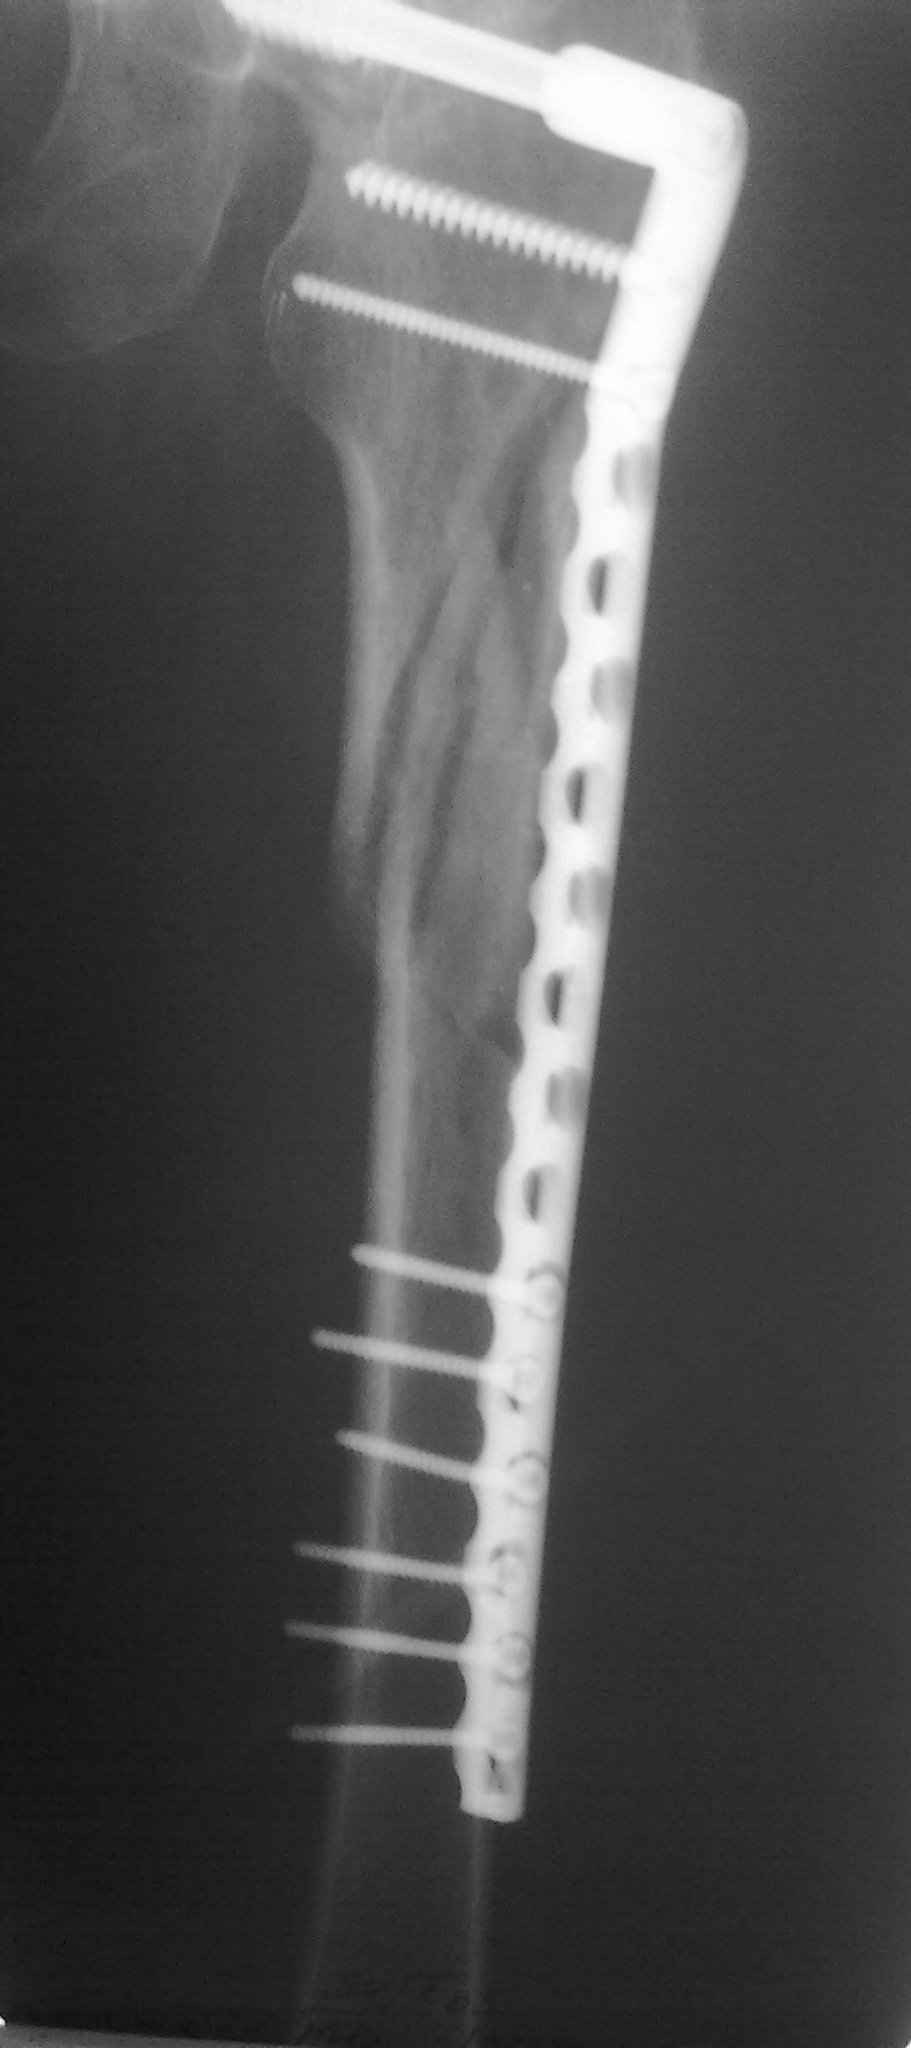

Пациент 83 года. Реконструктивный бедренный стержень Chm